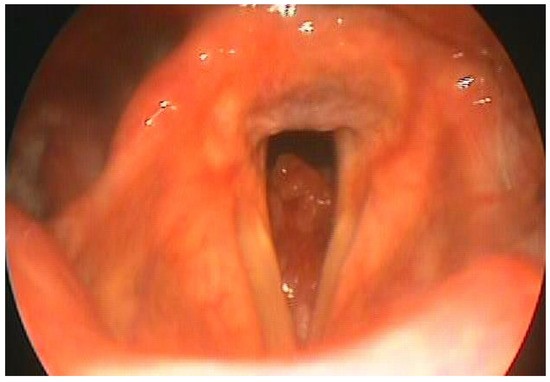

DG aged 60, underwent total laryngectomy and bilateral lateral cervical emptying for adenoid cystic carcinoma which had subglottic localization (Figure 1). The patient was an assiduous swimmer, enrolled in an amateur sports club, had achieved good results in numerous category competitions Seniors. After the operation, the patient experienced an initial period of depression despite the psychological support of our health facility and family members. After having overcome the distrust towards the resumption of sporting activity due to fears about its feasibility, he accepted the invitation to resume the sporting activity. A special device was therefore used (Figure 2). It establishes a watertight seal with a double-cuffed rigid tracheostomy tube. The configuration is similar to a snorkel device. The cuffed tracheostomy tube connects to a flexible hose with an attached mouthpiece. The mouthpiece is gripped with the teeth and sealed by the lips. Air flows through the nose, around the palate, into the mouth, through the Larkel tubing and into the lungs.

This device is designed for use in pool aquatic activities and is not recommended for activities such as ocean swimming. We prefer the flexible tube with a rigid walled cuffed tracheostomy tube. The rigid device allowed overinflation of the cuff to help immobilize the tube within the trachea, decreasing the likelihood of tube dislodgment and at the same time maintaining a patent lumen. The head and neck straps help to keep the device in proper position while swimming. The tracheal tube and cuff permitted a watertight seal while at the same time providing a conforming and comfortable fit.

Figure 2. Device used by the laryngectomee patient to swim.